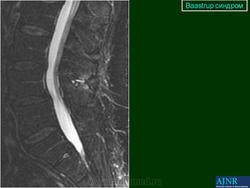

Baastrup синдром

"Бааструпа (Baastrup) болезнь, osteochondrosis interspinalis, arthrosis interspinal, kissing spine, описана в 1932 г. Характеризуется наличием хронических воспалительных изменений в остистых отростках позвонков. Вследствие этого возникают длительно удерживающиеся боли в поясничном отделе позвоночника, особенно при чрезмерном изгибе его кзади или чрезмерной нагрузке (поднимание тяжестей), с местной болезненностью в области остистых отростков. На рентгенограмме видны расширенные остистые отростки со склеротическими краями, иногда на верхнем или нижнем крае отростка остеофиты, которые могут даже соприкасаться между собой. Этиология-врожденное, неправильное развитие остистых отростков поясничных позвонков; заболевание наблюдается в определенном возрасте (30-40 лет) и у людей определенных профессий (грузчики).

Следует учитывать и относительную частоту неоартроза между остистыми отростками - межостистый диартроз (Meyer Н., 1924), «целующиеся отростки» (BrailsfordJ., 1929; Baastrup С, 1933). Синдром Бааструпа может сопровождать межпозвонковый остеохондроз (Forrai J., Tannai J., 1962). Е.С.Заславский и соавт. (1973) среди больных поясничным остеохондрозом определяли клинические и рентгенологические признаки синдрома Бааструпа в 5,5%. Боли при данном синдроме по характеру тупые, ноющие, сверлящие. Они усиливаются после длительного сидения, переноски тяжестей, при разгибании туловища. Выявляются болезненность и ограничение подвижности позвоночника (особенно в позе разгибания) на уровне пострадавших двигательных сегментов, болезненность при пальпации соответствующих межостистых промежутков. При вызывании феномена вибрационной отдачи в области поясничных межостистых связок боли, как правило, не только усиливаются, но и иррадиируют в пределах скле-ротома: в крестец, ягодицу, бедро. Инфильтрация же 1-2 мл 1% раствора новокаина межостистого промежутка быстро снимает эти феномены. Синдром связывают с поясничным гиперлордозом, структуральным сколиозом, переломом и вывихом позвонков, деформирующим спондилезом с аномальным увеличением остистых отростков. С.А.Рейн-берг (1964) относил изменения остистых отростков при данном синдроме к явлениям патологической перестройки костной ткани, обусловленной нагрузками чрезмерной силы на задние отделы позвоночного столба. Согласно N.Fellmann (1964), формирование сустава между остистыми отростками проходит следующие стадии: межостистый остеосклероз, фасетирование и склероз, тяжелое артрози-рование, анкилоз.

Baastrup синдром

http://www.ajronline.org/doi/full/10.2214/ajr.182.1.1820191

Болезнь Бааструпа

http://radsource.us/baastrups_disease/

Рисунок 1